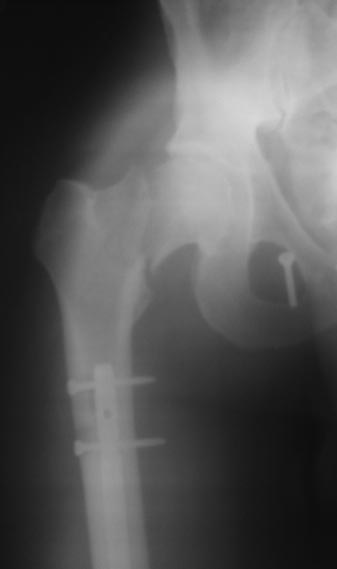

Приношу свои извинения за задержку с ответами на письма - две недели отсутствовал в отделении, не имея доступа к первоисточникам не видел смысла делиться соображениями. На форум, по моему предложению, случай представил младший коллега. Пишу об этом не с целью как-то уменьшить свою ответственность - ОПЕРИРОВАЛ Я, ТАКТИКУ ОПРЕДЕЛЯЛ Я, ПРОКСИМАЛЬНЫЙ ПЕРЕЛОМ ПРОПУСТИЛ Я... Теперь об одном обстоятельстве, которое меня не оправдывает, но может быть полезно в дальнейшей работе. В моей ошибке есть поучительный аспект: больной переведен в отделение 25.12.2013г., без снимков. На основании диагноза в выписке мы сняли таз (рис.1). Думаю, все согласятся, что картина там была, в отношении выявления перелома шейки несколько иная. В дальнейшем наше внимание занимала в первую очередь голень - высокий открытый перелом, массивная рвано-ушибленная рана мягких тканей вокруг бугристи, которая полностью не закрыта и по сегодня. Снимок, выставленный в первом сообщении, как "при поступлении" - от 15.12.2012г., т.е. сделан был при поступлении в ЦРБ. Родственники привезли его позже, мне пытались показать, но я сказал, что он уже не нужен - мы сделали свои. Думаю, что не проигнорировав его, я перелом бы заподозрил, верх переснял, не объяснял-бы себе картину после фиксации симфиза проекционным искажением.

По тазу - изолированный металоостеосинтез лонного сочленения двумя пластинами рассматривался как минимальный объем оперативного пособия, необходимый для активизации пациента в пределах постели. При этом было неверно оценено состояние крестцово-подвздошного сочленения, вывод о достаточной фиксации которого, образовавшимися рубцами, был сделан на основании прошедших двух месяцев с момента травмы, которые пациент находился на постельном режиме, т.к. сам по себе указанный срок сравним с периодом ограничения осевой нагрузки после операции на крестцово-подвздошном сочленении. К сожалению, не отличающийся конструктивностью поведения и эмоционально лабильный на фоне травматической болезни, больной, при первых признаках улучшения самочувствия, в виде отсутствия болевого синдрома при поворотах в кровати, начал неконтролируемую ходьбу на костылях по палате, закончившуюся «вырыванием» фиксатора из правой половины таза 05.03.2013г.